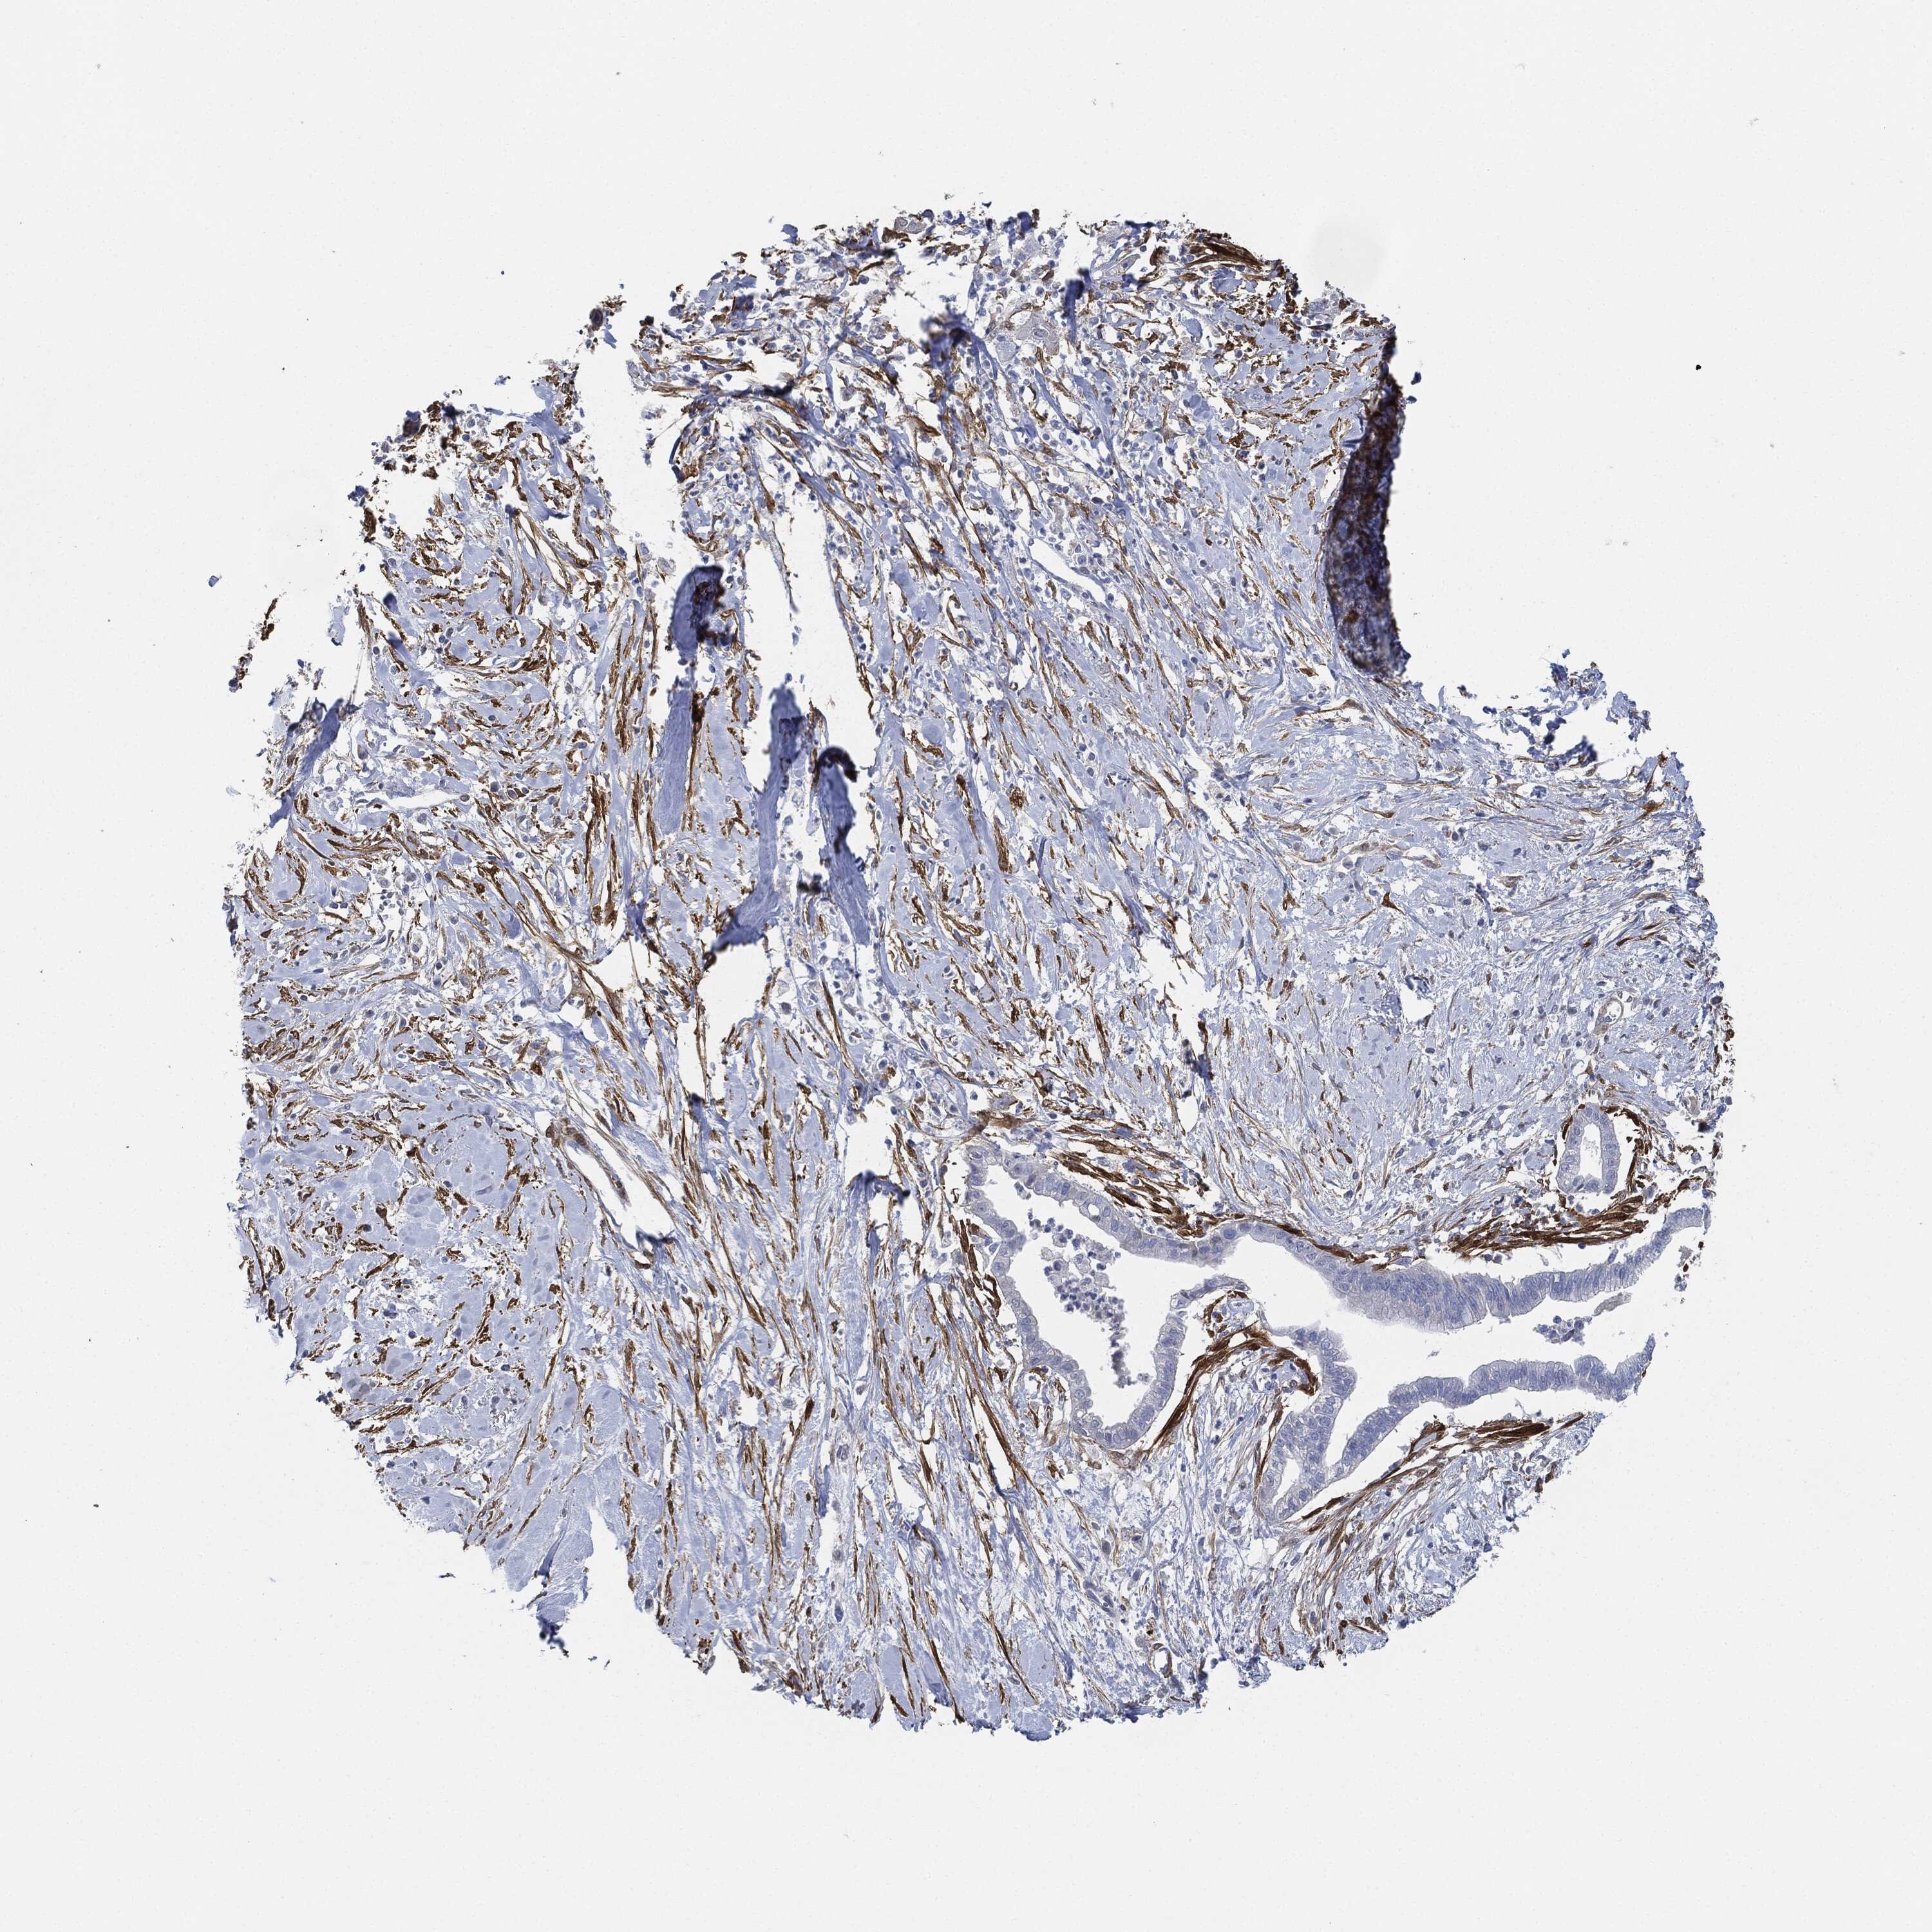

PANCREATIC CANCER - Protein expressioni

A mouse-over function shows sample information and annotation data. Click on an image to view it in a full screen mode. Samples can be filtered based on level of antibody staining by selecting one or several of the following categories: high, medium, low and not detected. The assay and annotation is described here.

Note that samples used for immunohistochemistry by the Human Protein Atlas do not correspond to samples in the TCGA dataset.

Antibody stainingi

Antibody staining in the annotated cell types in the current human tissue is reported as not detected, low, medium, or high, based on conventional immunohistochemistry profiling in selected tissues. This score is based on the combination of the staining intensity and fraction of stained cells.

Each image is clickable and will lead to virtual microscopy that enables deeper exploration of all samples and also displays staining intensity scores, fraction scores and subcellular localization as well as patient and tissue information for each sample.

Antibody HPA019467

Antibody HPA061657

Antibody CAB001447

Staining

High

Medium

Low

Not detected

Intensity

Strong

Moderate

Weak

Negative

Quantity

>75%

75%-25%

<25%

None

Location

Nuclear

Cytoplasmic/membranous

Cytoplasmic/membranous,nuclear

Adenocarcinoma, NOS